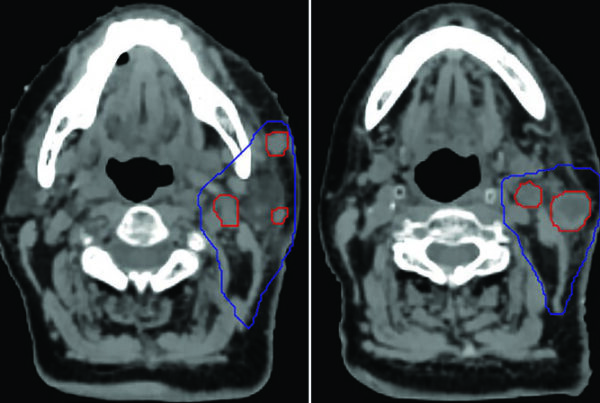

A diferença entre algoritmos se manifesta mais claramente em condições desafiadoras: campos pequenos, feixes de alta energia e heterogeneidades acentuadas — especialmente pulmão. A figura ao lado ilustra isso de forma dramática: para um feixe de 15 MV, campo 2,8×14 cm, 4 cm off-axis, atravessando 10 cm de pulmão (ρ = 0,2 g/cm³), as curvas de dose em profundidade divergem significativamente entre os algoritmos.

Monte Carlo ($MC_w$) serve como referência. O Collapsed Cone (CC-TMS, CC-PIN) acompanha razoavelmente bem, com desvios moderados na interface e dentro do pulmão. O AAA (AAA-ECL) segue de perto o CCC mas com desvios na interface tecido-pulmão. Já o Pencil Beam (PB-TMS, PBC-ECL) superestima a dose dentro do pulmão por uma margem clinicamente significativa e não consegue reproduzir a redução de dose lateral causada pela falta de equilíbrio eletrônico.

Na prática clínica, a escolha do algoritmo deve considerar o sítio anatômico e o cenário clínico. Para planejamentos em abdome, pelve ou cabeça e pescoço — onde as heterogeneidades são menos dramáticas — mesmo um pencil beam pode ser aceitável para planejamento forward, embora um algoritmo tipo “b” seja sempre preferível. Para pulmão, mama com campo tangencial passando por pulmão, mediastino, ou qualquer situação com campos pequenos de alta energia, um algoritmo tipo “b” (CCC, AAA, Monte Carlo ou Acuros) é essencial e não-negociável.